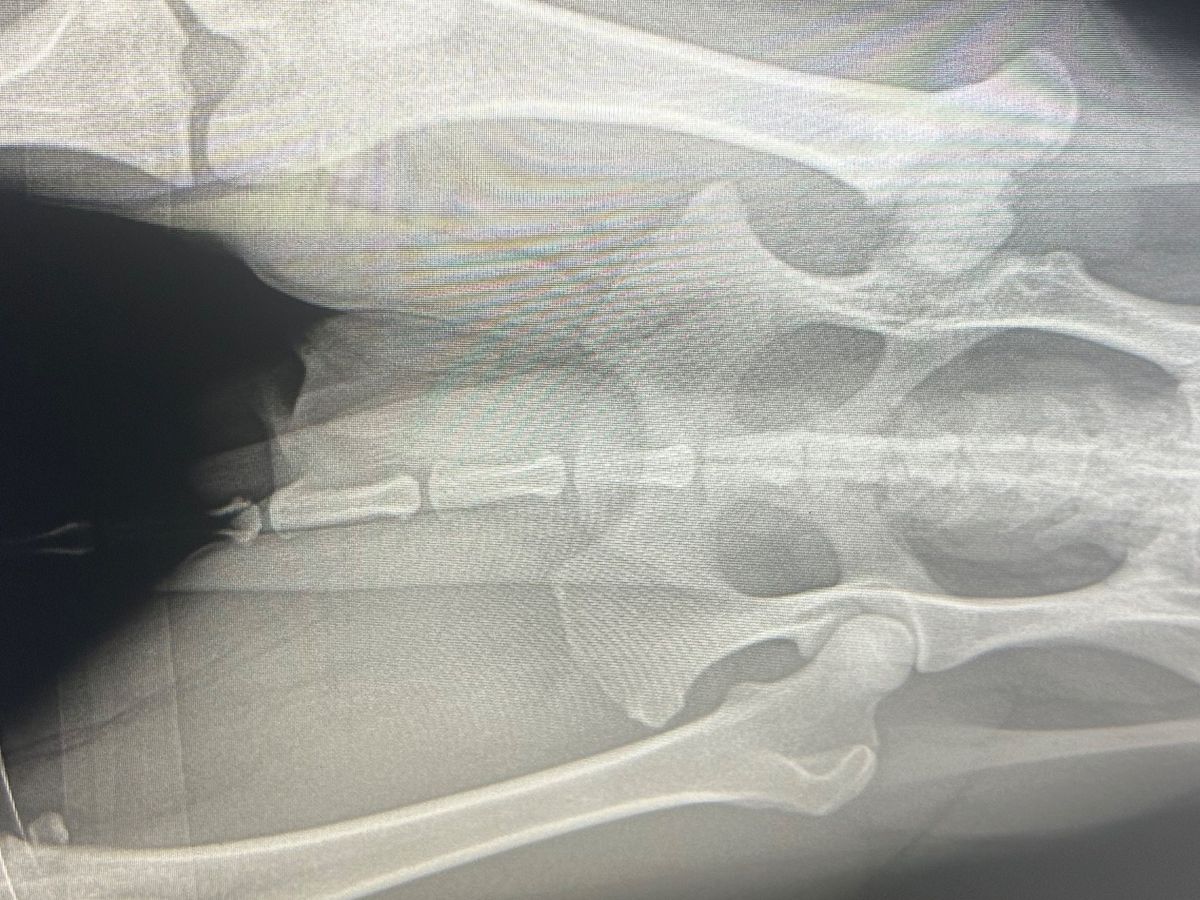

Chili is a barely 2 year old outgoing cattle dog that has been living most of his life in pain. When he was just a little 9 week old baby, an xtra large bully breed attacked him and left his hind leg permanently injured. We took him to 3 different vets who told us his leg was not broken or dislocated, just might be left with a little nerve damage. That was not the case, his leg was damaged much more than we had expected. Overtime, his limp never went away and there are days that he refuses to put pressure on it. We are here to try and raise funds in order to get chili his FHO surgery. I attached a photo of his xray in order to stress the issue as well as a few videos to example his discomfort. Your help and support is so much appreciated❤️we will share more photos after we get this boy healed up. Thank you so much.